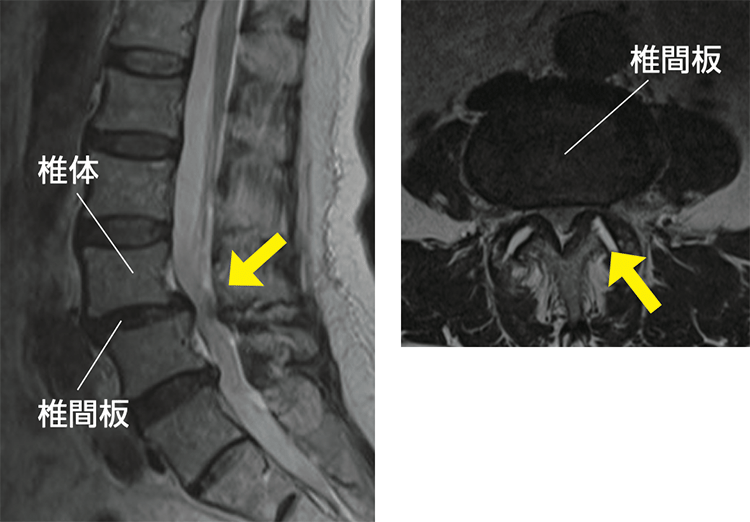

・MRI(磁気共鳴画像):脊柱管内の神経の状態を確認します(図2)。

脊柱管内で神経が圧迫されている様子がわかります(矢印)